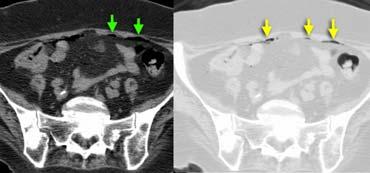

Viêm túi thừa sigma không biến chứng. Dấu hiệu mờ mỡ và dày thành đại tràng khu trú tại vùng có túi thừa. Không có hình thành áp xe.

Các biến chứng của viêm túi thừa như hình thành áp xe hoặc thủng, có thể được loại trừ tốt nhất bằng CT.

TRÁI: Viêm túi thừa sigma. Túi thừa (mũi tên) được bao quanh bởi lớp mỡ tăng tỷ trọng. Thành sigma dày. PHẢI: Ung thư sigma với dấu hiệu mờ mỡ giới hạn.

Một bẫy chẩn đoán quan trọng là ung thư đại tràng, có thể biểu hiện với các đặc điểm hình ảnh tương tự, đặc biệt khi ung thư đại tràng được bao quanh bởi dấu hiệu mờ mỡ do xâm lấn, phản ứng xơ hóa (desmoplastic reaction) hoặc viêm.

Thường không thể phân biệt một cách đáng tin cậy giữa viêm túi thừa và ung thư đại tràng, do đó chúng tôi thường xuyên đưa ung thư đại tràng vào chẩn đoán phân biệt của viêm túi thừa sigma.